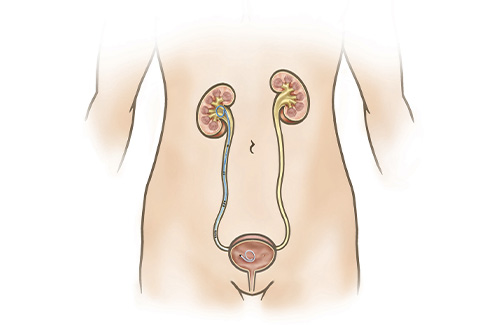

Ureteric Stent Going home Milton Keynes University Hospital new arrivals, Ureteral Stent Placement Memorial Sloan Kettering Cancer Center new arrivals, Ureteric Stent Patient Information Brochures Mater Group new arrivals, Ureteric stenting CIRSE new arrivals, Ureteroscopy and ureteric stenting for ureteric stones Urology new arrivals, Ureteric stent Macmillan Cancer Support new arrivals, IJMS Free Full Text Functional Properties of Polyurethane new arrivals, Ureteric Stent Insertion VIRQ new arrivals, Ureteric stent insertion Chelsea and Westminster Hospital NHS new arrivals, Consent Retrograde Ureteric Stent Insertion TeachMeSurgery new arrivals, Having a Ureteral Stent Saint Luke s Health System new arrivals, Ureteral Stents new arrivals, Dr Tim Nathan Urology Insertion and Removal of Ureteric Stents new arrivals, Ureteral stents are flexible tube like devices with holes new arrivals, Ureteral Stent for Parents Nemours KidsHealth new arrivals, Ureteral Stent Placement What is a ureteral stent Urology Austin new arrivals, Ureteral Stents What you need to know new arrivals, What Is Ureteral Stenting Procedure and Recovery new arrivals, Use of cystourethroscopy to remove an indwelling double J ureteral new arrivals, Ureteral Stent My Kidney Stone Boston Scientific new arrivals, Enhance Comfort and Recovery with Ureteric Stents new arrivals, Ureteral Stent Keystone Urology Specialists new arrivals, Abdominal X ray Artifacts Renal and ureteric stents new arrivals, What to Expect from a Ureteral Stent Advanced Urology new arrivals, Ureteric Stents new arrivals, Your Guide to Ureteral Stents For Kidney Stones Worst Pain Ever new arrivals, Cystoscopy and Ureteral Stent Placement new arrivals, Determination of urinary prostaglandin E2 as a potential biomarker new arrivals, Nephrostomy and ureteric stenting CIRSE new arrivals, Outcomes of outpatient ureteral stenting without fluoroscopy at new arrivals, Ureteral Stents Boston Scientific new arrivals, Ureteral Stent Placement new arrivals, Surface engineered biomaterials and ureteral stents inhibiting new arrivals, Ureteric Stent Insertion OneWelbeck Men s Health new arrivals, Calcified ureteric stent Radiology Case Radiopaedia new arrivals.